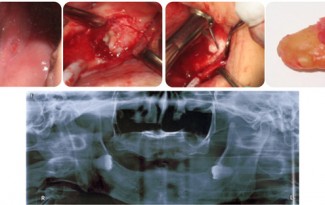

Extraction with root tip Fracture

This emergency patient arrived at my office in pain. He was on vacation from London. His dentist removed a portion of this lower left molar but was going to refer the patient to a specialist to complete the extraction. The … Continue reading